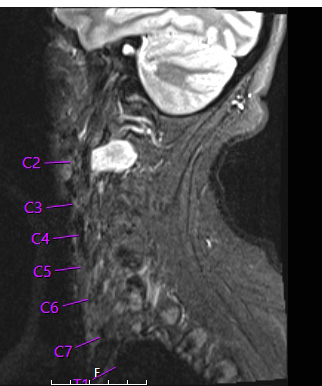

Case 32 History ---- The patient is a 46 year old woman with a C2 nerve tumor. Operative procedure: Right C2 nerve tumor resection. ---- 32A1 STIR scan demonstrates a hyperintense mass at the C2 cord level.